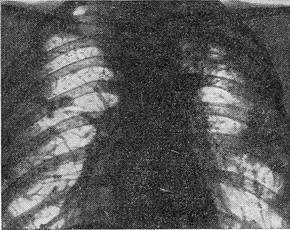

![]() Рис. 1. Гематогенно-дисемінований туберкульоз. |

При хронічних формах дисемінованого туберкульозу дрібні однотипні вогнища з'єднуються фіброзними тяжами (рис. 1). Найбільш часто фиброзноочаговые форми туберкульозу локалізуються у верхніх частках легень. Тут же зазвичай розташовуються і каверни. В нижніх частках легень частіше розвивається мелкосетчатый пневмосклероз.